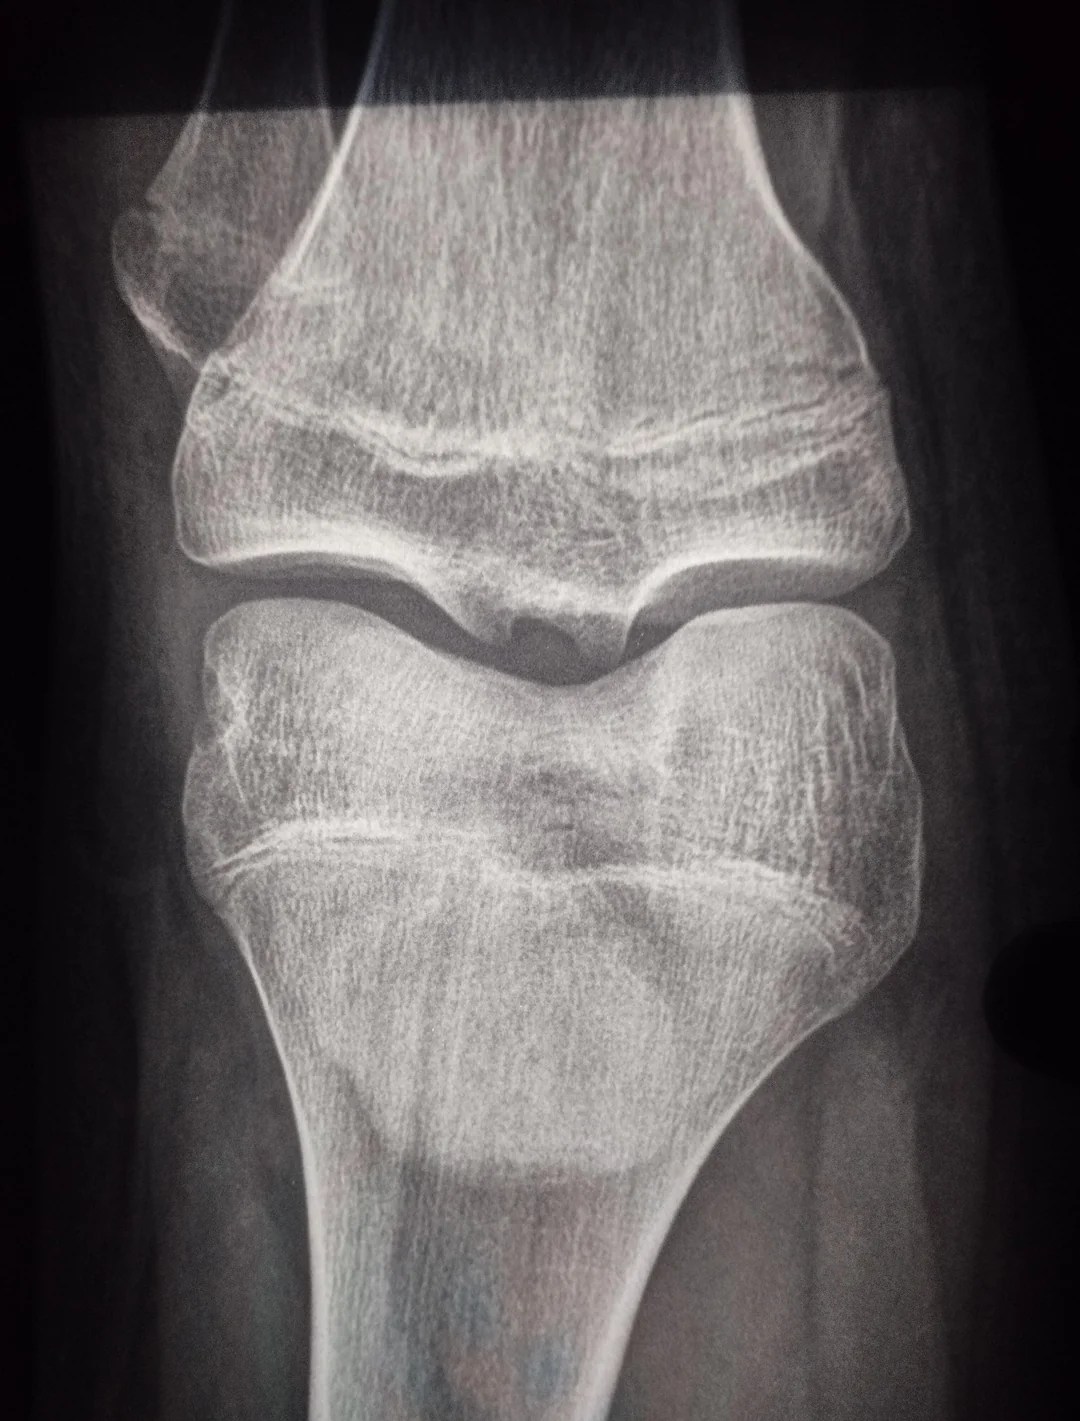

Growth Plates: When Do Growth Plates Close?